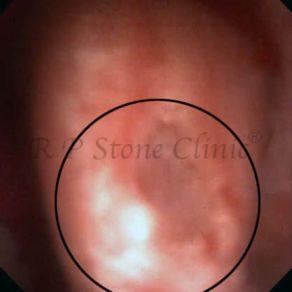

Kidney stone is a solid mass of CRYSTALS. It is the process of crystallization which initiates the formation of kidney stones. This happens in nephrons or units of kidney. Once a small crystal is formed, it can both grow & unite with other crystals leading to the formation of small concretion which eventually forms a stone. Once these large crystals detach from the collecting ducts, the process of stone formation starts in the renal collecting system. A recurrent kidney stone former is advised to know a little bit about something known as Randall’s plaque. Alexander Randall discovered plaques on the renal papillae eight decades back based on examination of 1154 pairs of autopsied Kidneys. He described these renal papillary lesions as cream colored or milk patch areas composed of calcium phosphate & calcium carbonate. These plaques could act as NIDUS for formation of KIDNEY STONE. Calcium Oxalate stone can form on this nidus & then detaches from this plaque to become a free floating stone in the collecting system of kidney

These images are taken as snap shots from the video recording of RIRS Surgery done at our hospital. These are Randall’s Plaques seen with Digital FLEX XC & Digital FLEX XC S. The cream or whitish patches are seen on the tips of RENAL PAPILLAE as seen in images below.

Randall’s Plaques may lead to the formation of Stones.